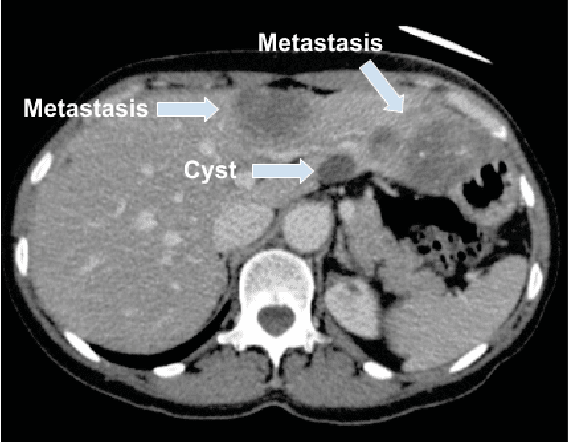

Abstract:Colorectal liver metastasis is one of most aggressive liver malignancies. While the definition of lesion type based on CT images determines the diagnosis and therapeutic strategy, the discrimination between cancerous and non-cancerous lesions are critical and requires highly skilled expertise, experience and time. In the present work we introduce an end-to-end deep learning approach to assist in the discrimination between liver metastases from colorectal cancer and benign cysts in abdominal CT images of the liver. Our approach incorporates the efficient feature extraction of InceptionV3 combined with residual connections and pre-trained weights from ImageNet. The architecture also includes fully connected classification layers to generate a probabilistic output of lesion type. We use an in-house clinical biobank with 230 liver lesions originating from 63 patients. With an accuracy of 0.96 and a F1-score of 0.92, the results obtained with the proposed approach surpasses state of the art methods. Our work provides the basis for incorporating machine learning tools in specialized radiology software to assist physicians in the early detection and treatment of liver lesions.